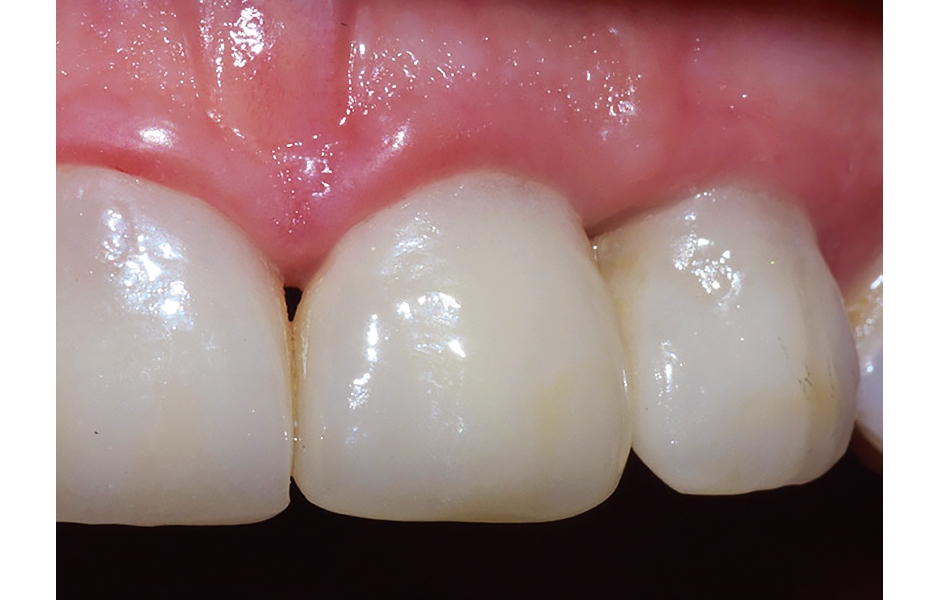

- Obr. 17: Finální zirkonové korunky byly nasazeny 3 měsíce po zavedení implantátů – snímek zachycuje situaci 1 rok po operaci.